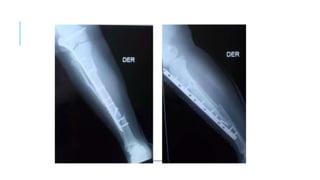

La distancia entre los tonillos proximal y distal mas próximos al foco

de fractura es definido como el área de trabajo de una placa.

El área de trabajo de la placa influye en la rigidez del constructo,

EL AREA DE TRABAJO ES LA DISTANCIA

ENTRE LOS PRIMEROS DOS TORNILLOS DE

BLOQUEO LOCALIZADOS A CADA LADO

DE LA FRACTURA Y ES EL AREA DONDE

EL ESTRÉS ES APLICADO